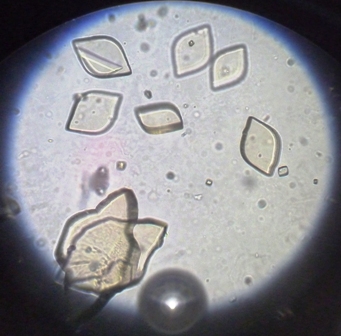

Normal Acidic Crystals

Calcium oxalate and uric acid

the envelope ones aka

Calcium oxalate

What causes calcium oxalate?

Foods high in oxalic acid, antifreeze posioning, main culprit of renal calculi

and these r:

Uric Acid

3 forms of calcium oxalate

envelope, oval, dumbbell